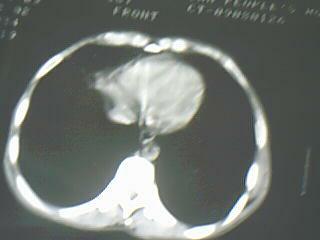

以下是引用随光逐影在2009-8-7 15:40:00的发言:[br]考虑右肺继发性肺结核并右肺上叶空洞形成,两肺支气管播散;不排除右肺上叶空洞内霉菌感染可能。

以下是引用jiangjing在2009-8-7 14:38:00的发言:[br]右上肺张力空洞,酐珞坏死灶,支气管扩张,多发播散灶,纵膈淋巴结显示,胸膜增厚---结核